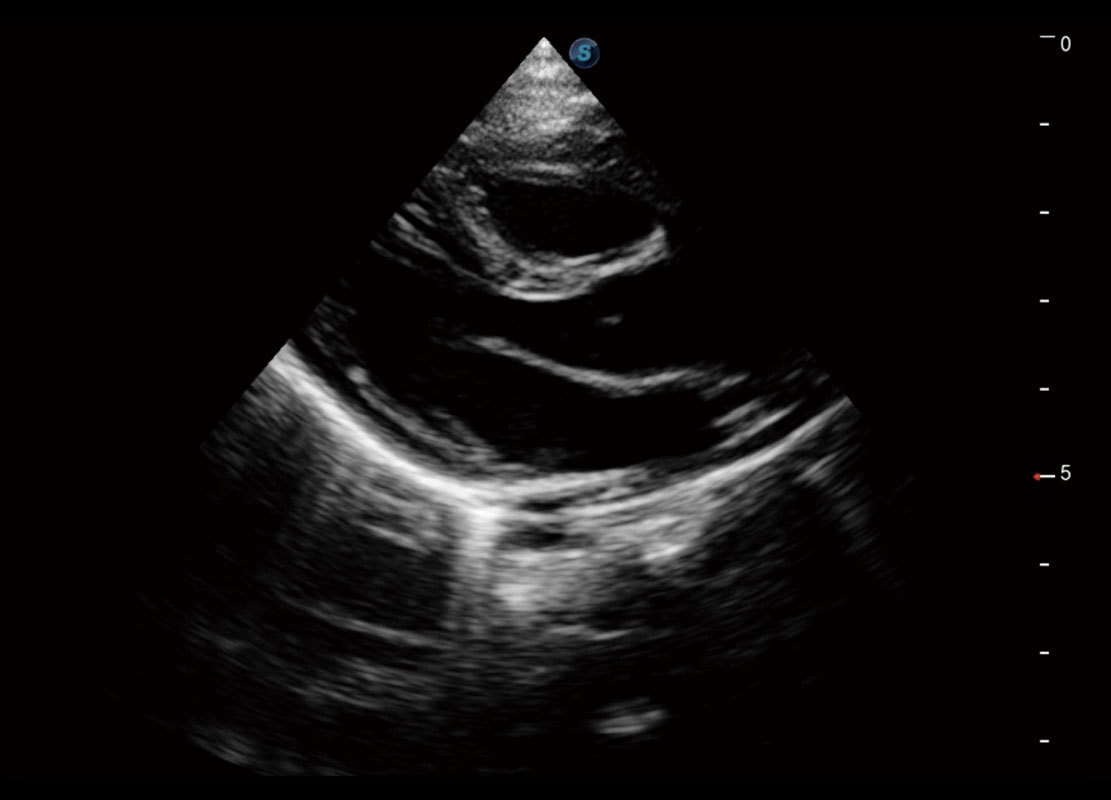

P60搭载一系列胎儿心脏成像技术,实现精细的胎儿心脏评估。

四腔切面

四腔心血流

右室双出口

胎心容积成像

新生儿心脏